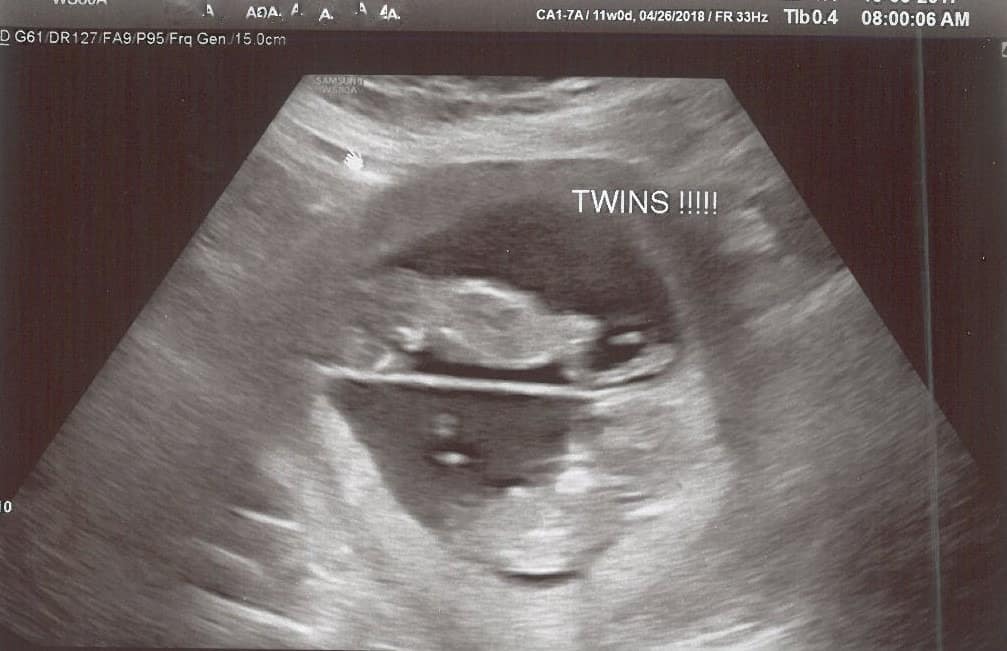

Ultrasound Photos at 11 Weeks Pregnant With Twins